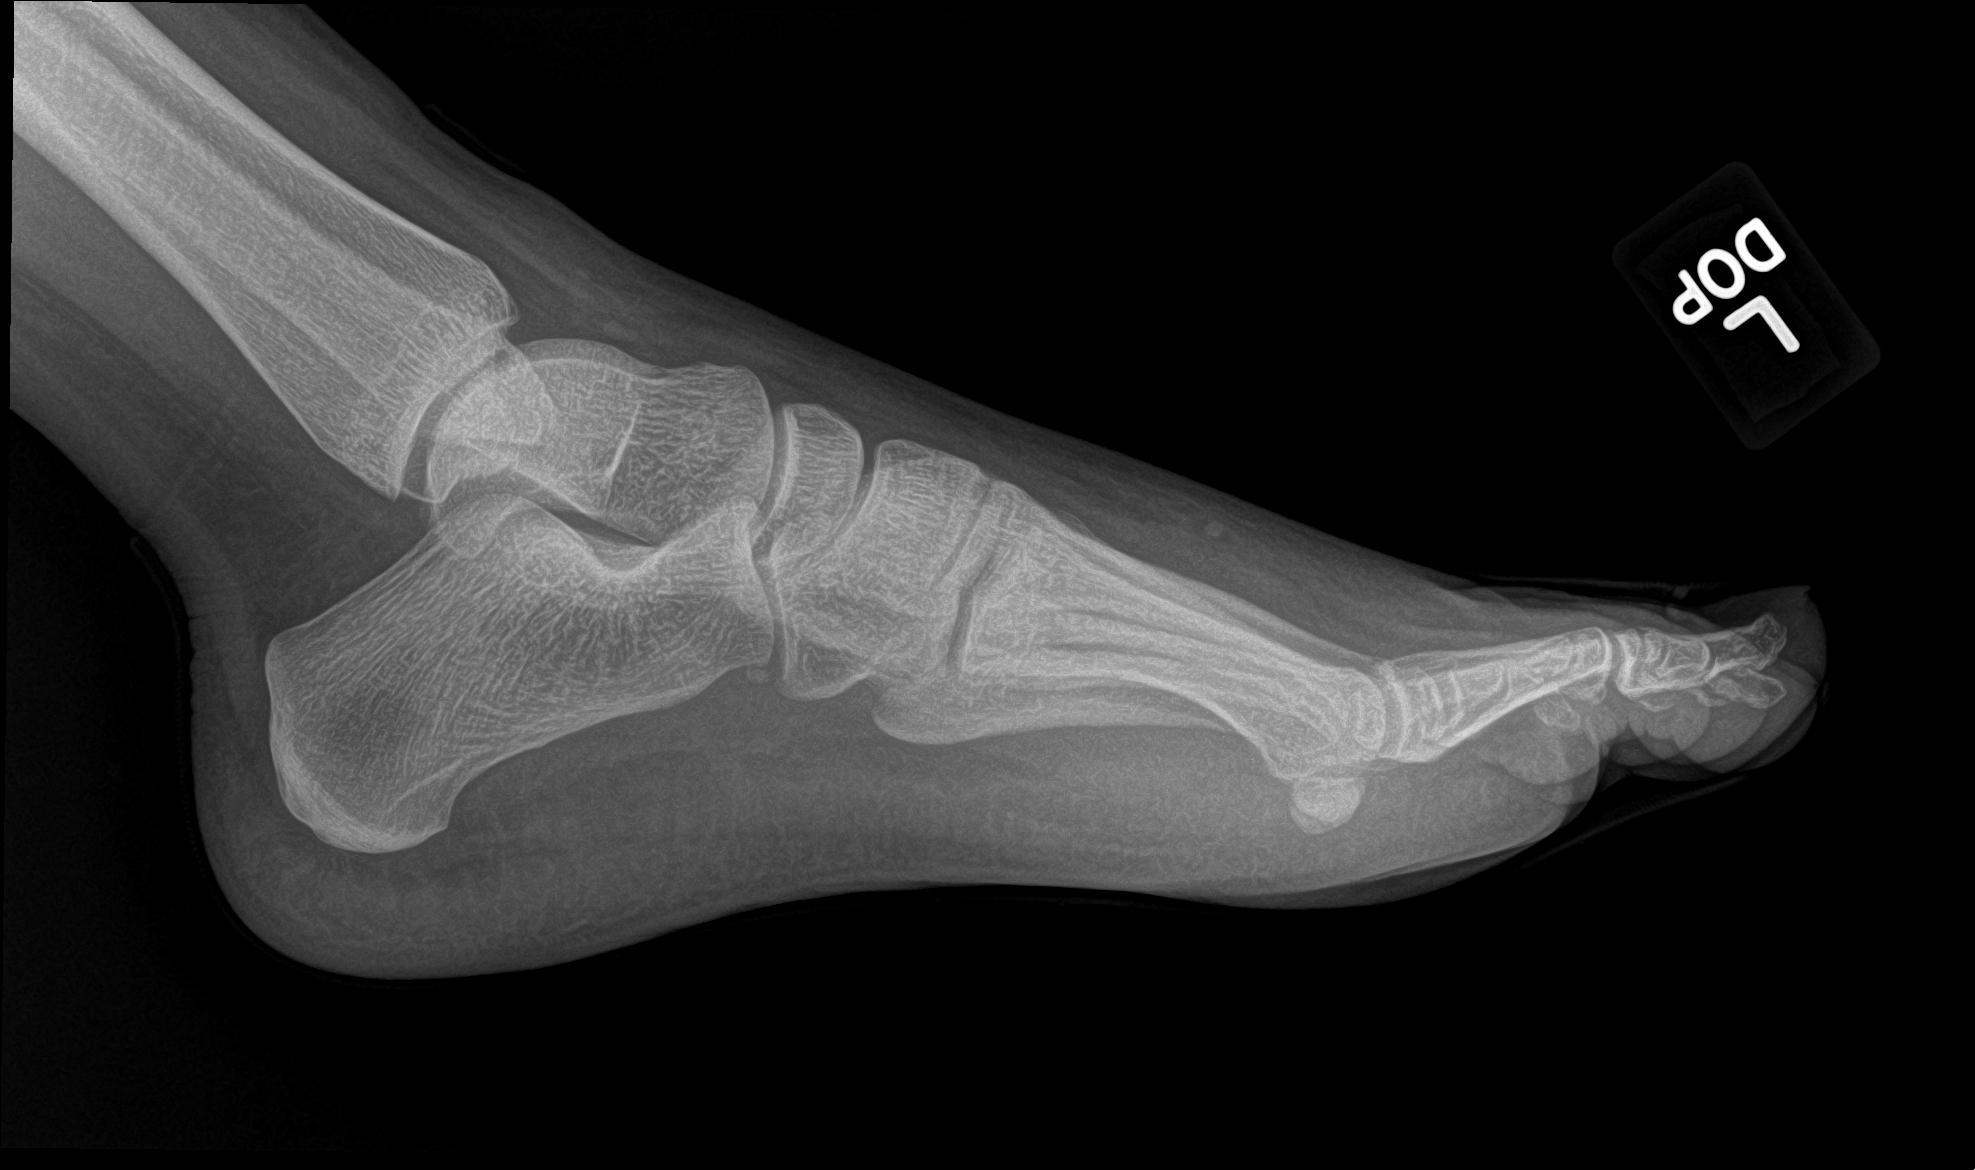

A 21 year old female with left forefoot pain after rolling her foot 2 weeks ago.

base of the 3rd metatarsal fracture